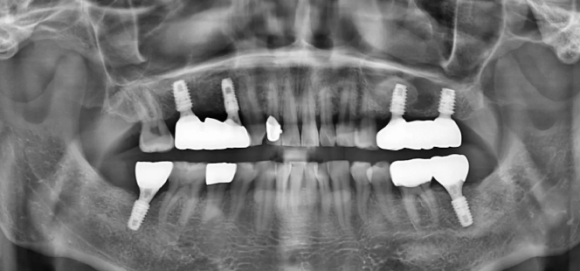

(치료 전) 파노라마

(치료 후) 임플란트,보철 등 여러 치료